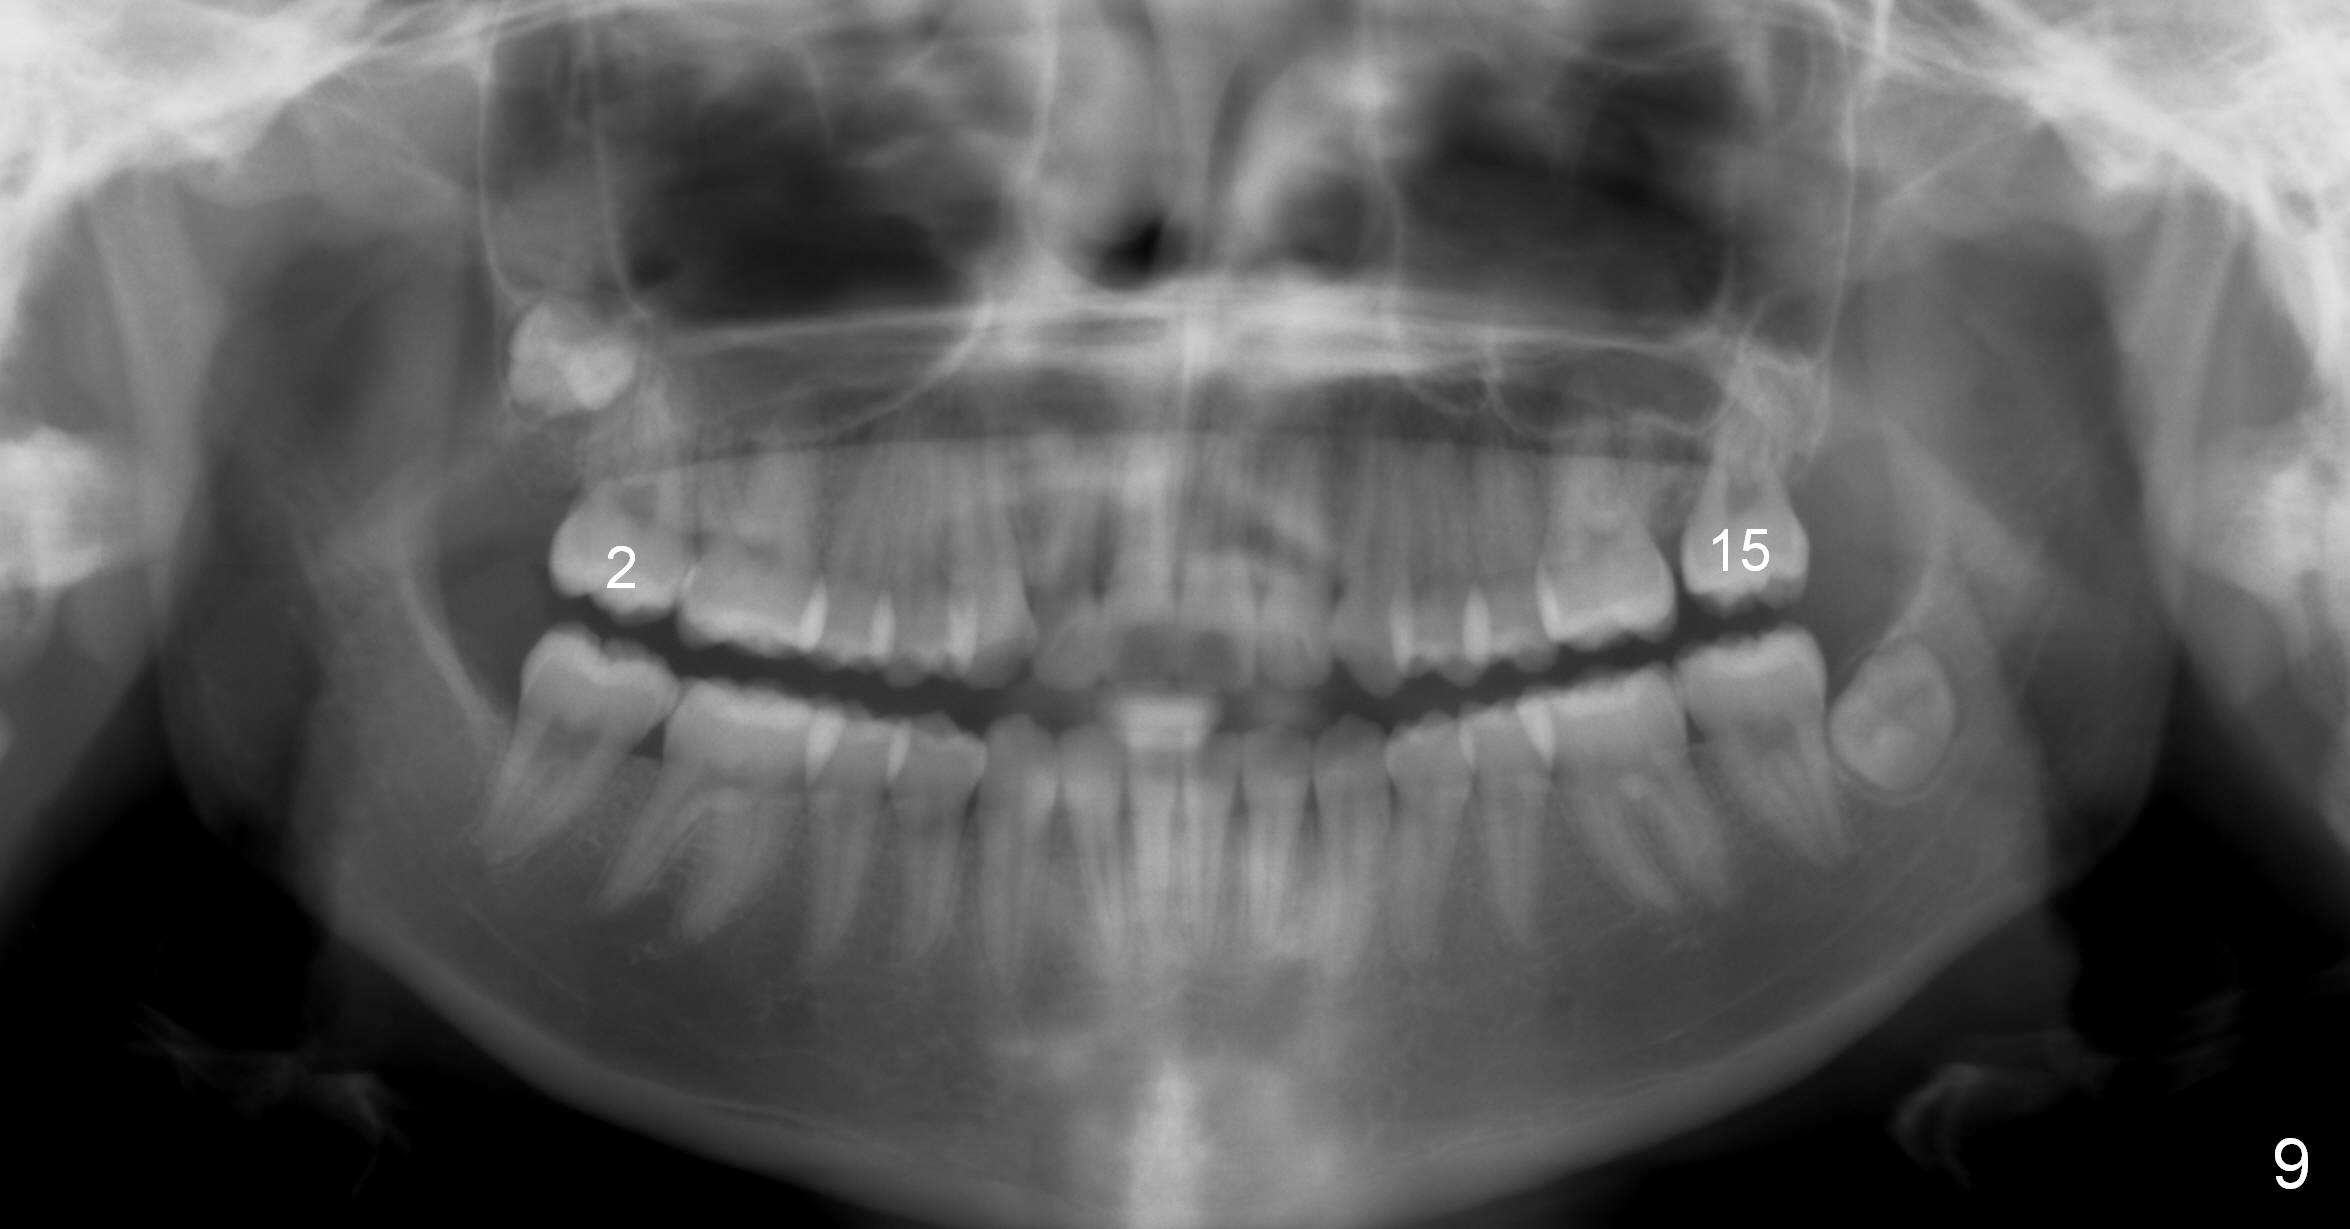

Treatment finishes in 2 years.  The patient (15 years 2 months old) returns for follow up 3 months post debanding (Fig.9, compare to preop).  Uncover Last Next Xin Wei, DDS, PhD, MS 1st edition 11/28/2015, last revision 12/15/2019